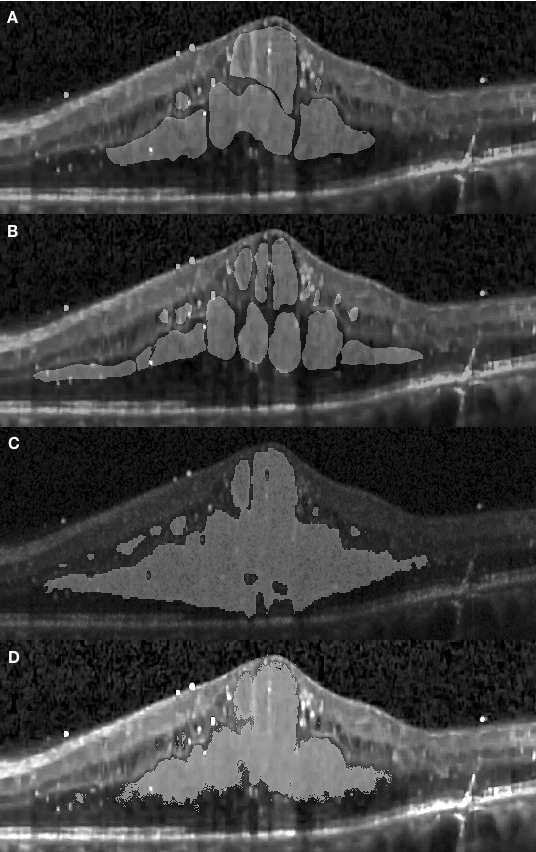

In Fig. 4.3 (D) we demonstrate results of our framework operating on images depicting more severe morphological conditions. The retinal layer in Fig. 4.3 (A) was destroyed by a large section of edema which mixed various shapes of fluid and concrete edemas. The central fluid section is fused with the concrete part on both the left and the right-hand side of the images, where both sections were successfully segmented by our approach. It can be seen that our approach shows that the segmentation achieved is consistent with the appearance of the pathology and accurately covers the entire region. Several small sections were also well segmented but some slimmer region is not detected since it is too slim to be perceived by the network. In Fig. 4.5, we present additional results from severe conditions that present complex structure appearances.

Figure 4.5 depicts the comparison of our method with the one reported in Chiu et al. [19] for three segmentation attempts carried out complex retinopathy conditions. It is found that Chiu’s method performs a slight over-segmentation near the bottom area. The segmentation results carried out with our method are closer to those which have been manually segmented. In Fig. 4.6, three images are shown which depict segmentation results on concrete and non-obvious fluid edema. The over-segmentation noted earlier can also be observed , as well as a false segmentation happening in the region on the left-hand side. Again, the results obtained with our method have a better agreement with those obtained via manual segmentation. Furthermore, our results are more adherent to target based on image content. This is also found in Fig. 4.7 where additional results are presented from the segmentation of an example of fluid edema. Quantitatively, we compared the Dice overlap coefficient and -value of Wilcoxon matched-pairs test for the DME region. Dice coefficients were calculated for all 10 patients and the process was repeated as per[19]. Specifically, the Dice coefficient was calculated based on all test images and the Wilcoxon matched-pairs test was calculated based on the mean Dice coefficient across all patients for our automated method and for the corresponding results from two graders. It was found that the Dice coefficient of our approach is standing for mean and standard deviation which outperforms reported in [19] (the higher, the better). Both methods are comparable with the Dice coefficient between manual graders ( ). The -value for our approach is , which is also better than reported in Chiu et al. [19] (where a coefficient value of indicates perfect agreement).